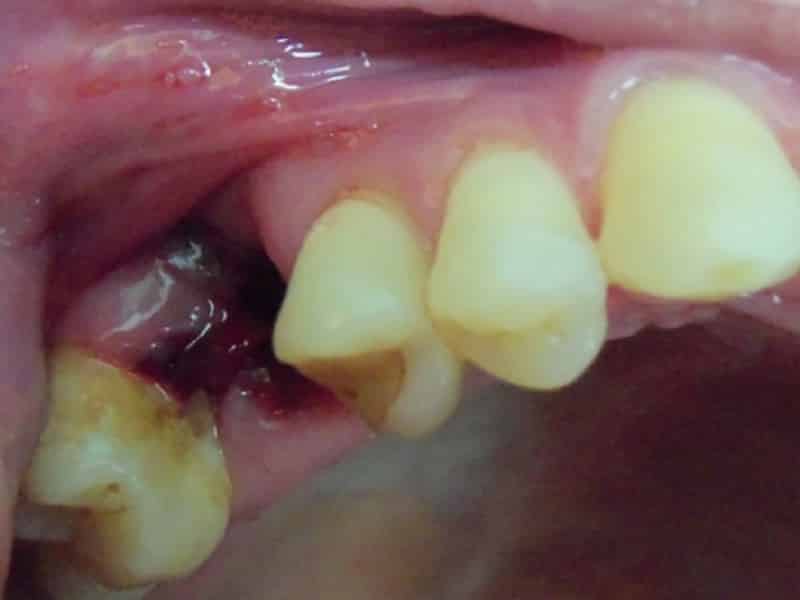

Скорость восстановления после удаления зуба зависит от нескольких факторов, включая физиологические особенности пациента, опыт врача, место удаления зуба и возможные осложнения операции. В некоторых случаях, когда зуб уже отсутствует или разрушается во время операции, стоматолог может прибегнуть к разрезанию десны, что может замедлить процесс заживления. После удаления зуба образуется кровяной сгусток, который играет роль барьера для защиты от инфекций. Этот сгусток необходимо оставить на месте, чтобы предотвратить воспалительные процессы. В течение нескольких дней сгусток меняет цвет и постепенно заживает, а открытая рана затягивается грануляционной тканью. Полное заживление мягких тканей обычно занимает около 2-3 недель, но процесс формирования новой костной ткани может продолжаться несколько месяцев. После удаления зуба может наблюдаться отёк десны, который обычно сходит через несколько дней.

В большинстве случаев эти осложнения возникают из-за заражения лунки болезнетворными бактериями. Чтобы избежать этого, необходимо тщательно ухаживать за полостью рта и осторожно чистить зубы, чтобы не повредить заживающую десну.

При накоплении гнойных образований следует немедленно обратиться к врачу. Кроме того, существует возможность вторичного заражения, когда инфекция проникает в десну снаружи. Основные причины внешнего заражения раны включают отсутствие защитного тромба, проникновение зараженных тел в рану (части зубов, костей, зубного камня и т. д.) и невыполнение инструкций врача по уходу за поврежденной десной.